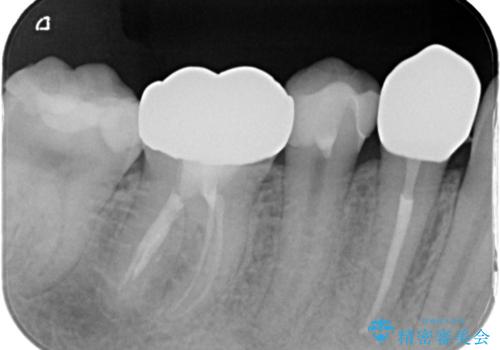

- 右下が痛くて噛めないとの理由で来院された患者様です。レントゲン撮影、歯髄の診断等から、根管治療、歯髄保存療法が必要と判断し、治療後に丈夫で審美性に優れたセラミックインレー、フルジルコニアクラウンを被せました。

治療後は痛みもなくなり、経過も良好でキレイな被せ物にも満足いただけました。